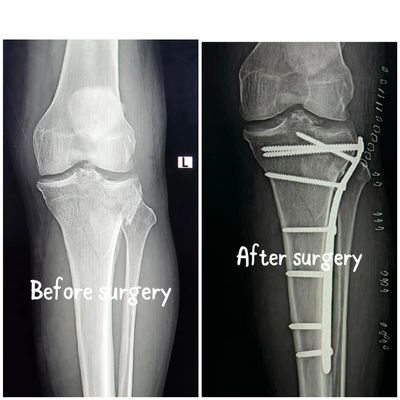

• Surgical Fixation: Advanced use of internal fixation (plates and screws) and intramedullary nailing for long bone fractures.